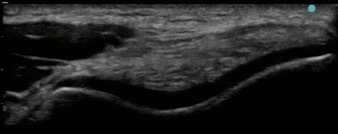

Knee Anterior Trochlear Cartilage 2 Image